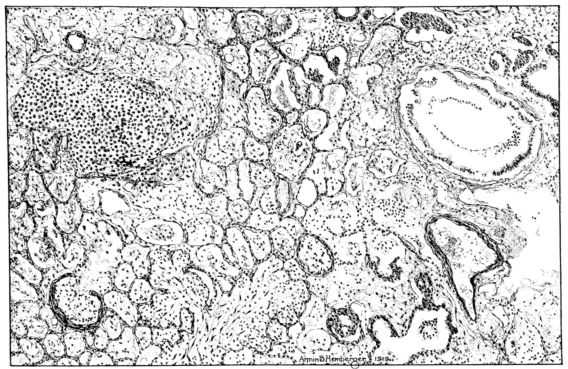

(3) ORGANIZATION OF BRONCHIOLAR AND PNEUMONIC PROCESSES.

The processes described for the preceding group which involve not only the alveoli, but also the bronchi and the bronchioles, were predicted from the extensive hyalinization of these structures—a characteristic change in the more fulminating and acute phases of the disease. Likewise, it can be predicted that where death does not terminate the process such lesions will be followed by organization, which, by converting the exudate into scar, will produce deformities and offer serious mechanical interference with the ingress and egress of alveolar air and similar interference with the flow of blood through the pulmonary circulation (82).

Microscopic examination of sections from the lung showed an extensive bronchopneumonia. The alveoli of an occasional group of lobules were filled with serum or red blood cells, while still other areas showed foci of necrotizing pneumonia, actual miliary abscesses in which there were large clumps of bacteria (Fig. XLI). Throughout the sections, however, the striking change was an organization of the exudate, which varied from a few fibroblasts to a well defined connective tissue almost obliterating the normal architecture (Figs. XLI and XLIV). The alveolar walls in some 28areas showed edema only, in others they were almost replaced by a thin line of fibrous tissue, and in still others, by a hyperplasia of the epithelium which almost filled their lumina. The bronchi exhibited similar changes, their lumina were filled with an exudate of desquamated epithelium and leucocytes, which in some places was organizing (Fig. XI), and there was a regeneration of epithelium evidenced by a piling up of the cells and the presence of mitotic figures in them. The interstitial tissue showed some edema. The tracheal epithelium was intact, but a few leucocytes and lymphocytes were scattered through the submucosa.

Microscopic examination of the lung showed the alveoli filled with an acute inflammatory exudate in many stages of degeneration and hyalinization (Fig. XLII). Abscesses were frequent, but were for the most part small. A similar necrotic mass was contained in the bronchi. There were, however, features of the microscopic picture that outweighed those already described. The alveolar and bronchiolar exudates were everywhere being invaded by a young granulation tissue, rich in fibroblasts and capillaries. Mononuclear cells abounded in the new tissue. Even more striking than the mesodermal new growth was the epithelial proliferation which could be seen in many areas. It not only attempted to cover the denuded bronchial surfaces, but stretched over masses of exudate and granulation in the lumina and extended in tongue-like projections for a considerable distance into the surrounding lung tissue (Fig. XLVIII).